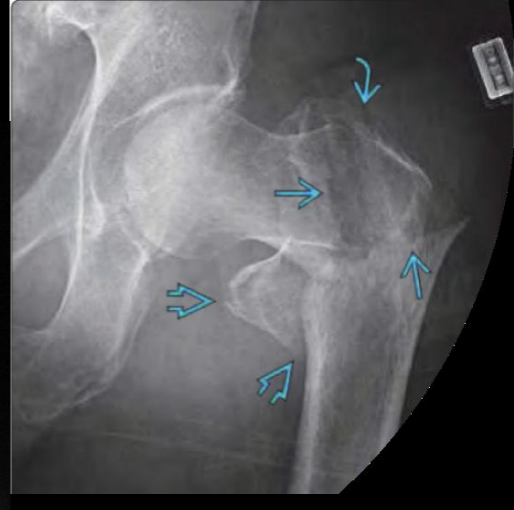

Q

A

Cabeza

Cuello

Intertrocantereo

Subtrocantereas

Fx cuello femoral

Fx intertrocanterica

How well did you know this?